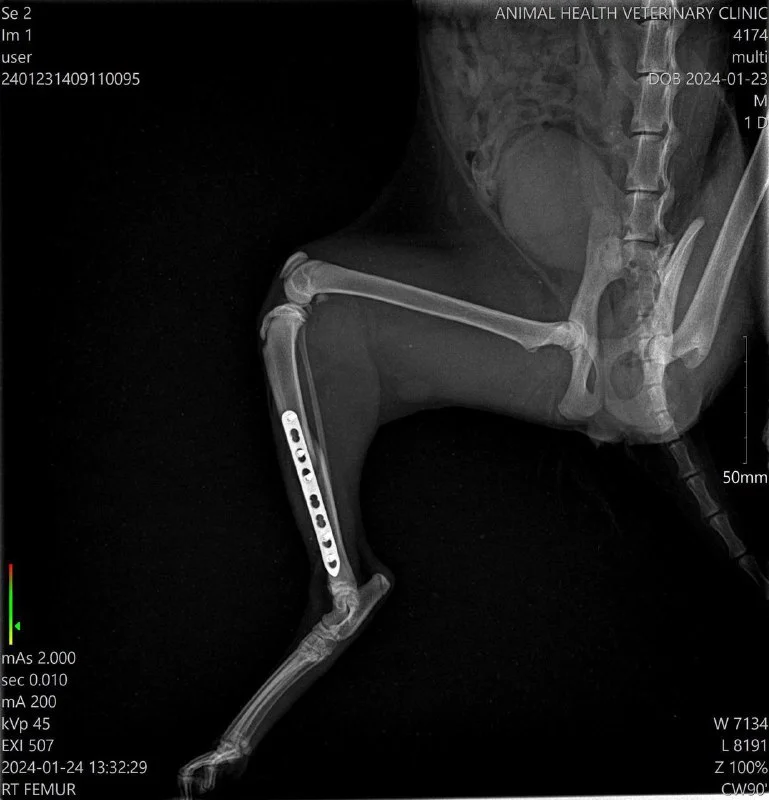

Добрый вечер! На днях увидела кошечку Лисси, которая живет в нашей колонии, она заднюю лапу волочила по земле. Нужно было срочно действовать и соседка Анастасия согласилась отвезти в клинику. Сделали рентген , оказался перелом задней лапки. Вчера была сделана операция , поставили пластины и стерилизовали сразу. Сегодня Лисси выписали. Нужна долгая реабилитация, но самое главное , она в безопасности и под контролем.

Лисси невероятно ласковая и благодарная.

Друзья, если у Вас есть возможность, помогите с оплатой операции. Ей предстоит долгая реабилитация.

Заранее благодарю!

Revolut 96586890

Bank of Cyprus CY46002001950000357027586398

PayPal [email protected]